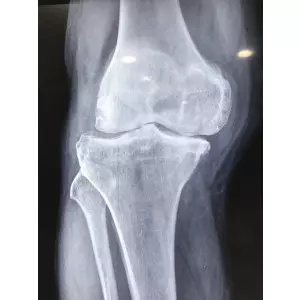

Jay Patel - USA